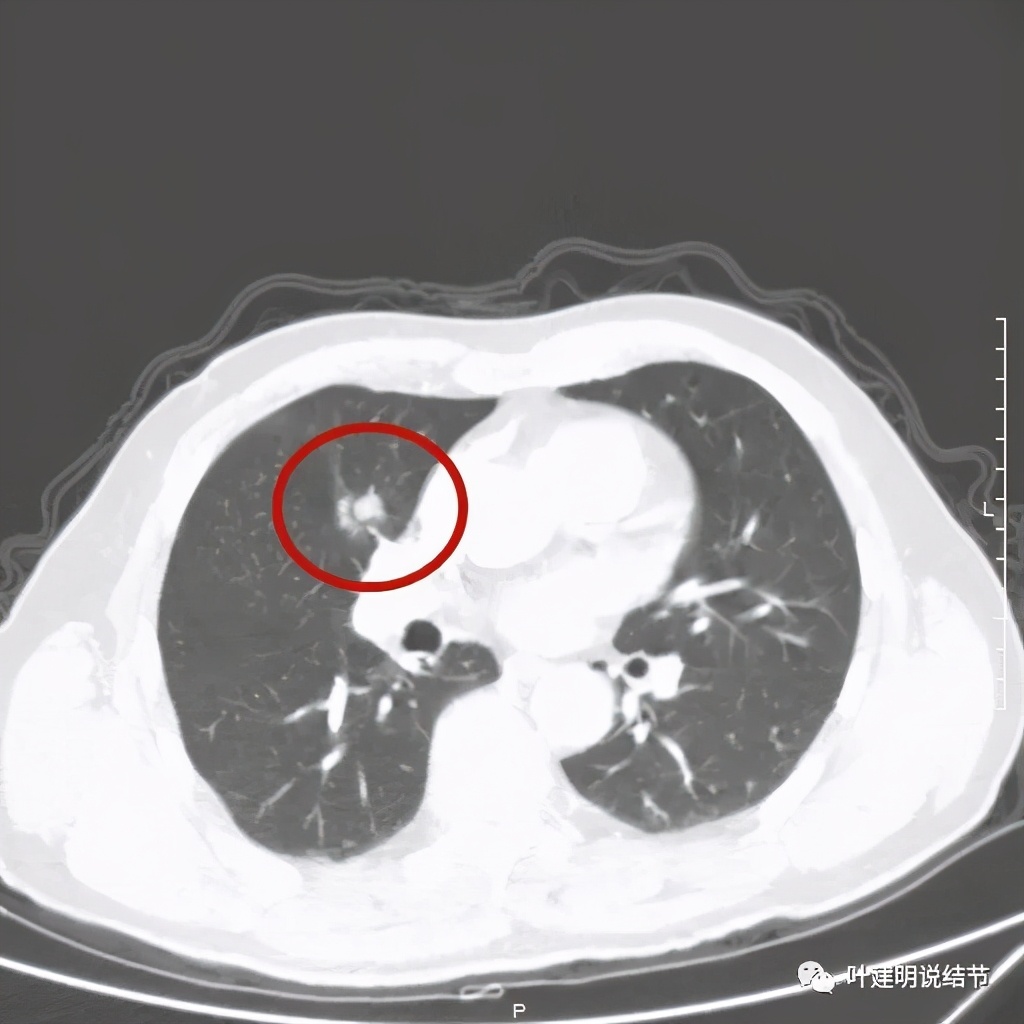

病灶有分叶及胸膜牵拉

以上几图示病灶膨胀感明显,无卫星灶,周围无渗出性改变

上图粉色箭头示细毛刺征,蓝色似支气管截断,红色示病灶膨胀性明显